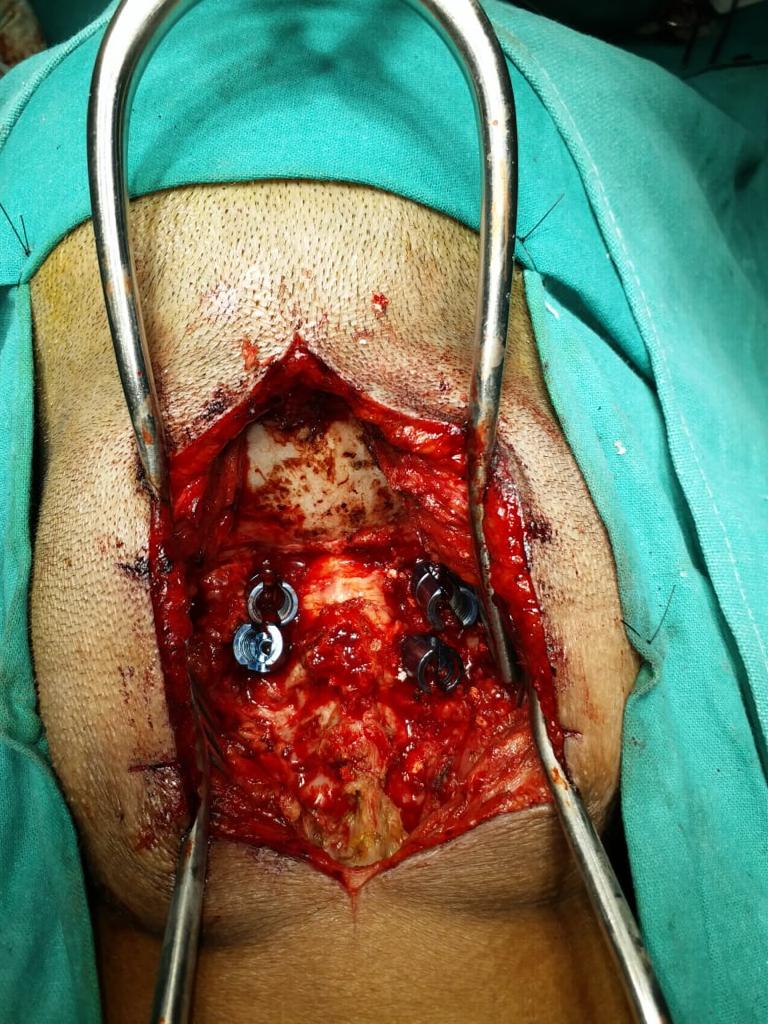

Cases